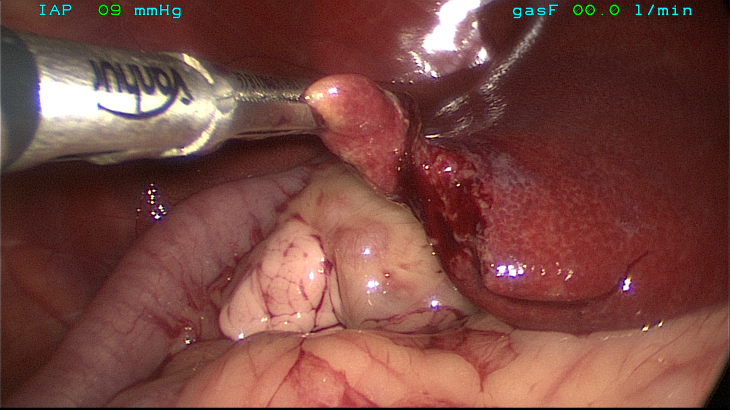

MIS is also becoming increasingly popular among veterinary surgeons. The principles of MIS are that it provides a highly magnified, well-lit image of a region of anatomy that would otherwise require a significantly larger incision and higher morbidity for the equivalent procedure to be performed as an “open surgery”. This, therefore,

MIS is also becoming increasingly popular among veterinary surgeons. The principles of MIS are that it provides a highly magnified, well-lit image of a region of anatomy that would otherwise require a significantly larger incision and higher morbidity for the equivalent procedure to be performed as an “open surgery”. This, therefore,

allows the MIS patients to recover faster and experience less postoperative pain than those animals who undergo equivalent open surgery. There are also significant advantages to the surgeon in that it is often easier to access certain areas of anatomy using MIS, procedures are often faster than the equivalent open surgery and anatomy is greatly magnified potentially leading to an increased sensitivity in detecting early disease.

There have been significant advances made in the field of MIS. Laparoscopy/Thoracoscopy is no longer limited to being purely diagnostic. Therapeutic interventions such as cholecystectomy, adrenalectomy, pericardiectomy and thoracic duct ligation can now be safely performed providing that appropriate cases are selected.